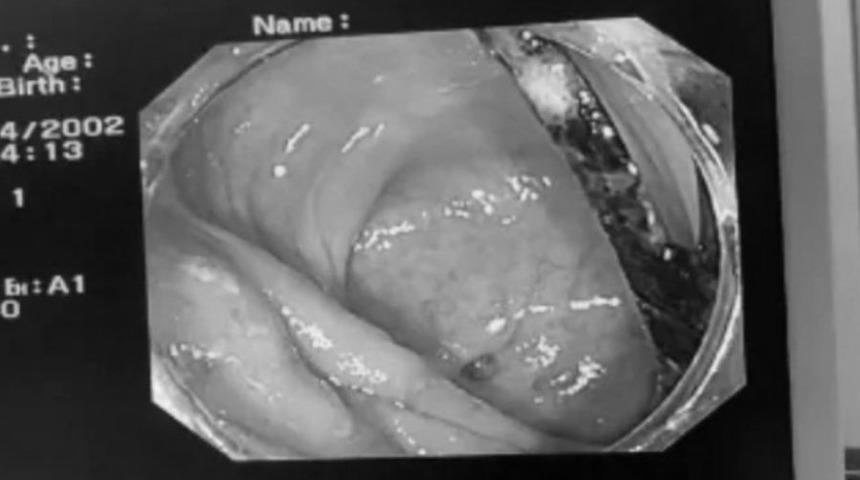

MYNET|DIŞ HABERLER Çin'in Guangdong eyaletinin Foshan bölgesinde ismi açıklanmayan bir hasta aylarca devam eden mide ağrısı nedeniyle hastanelik oldu. Endoskopik cerrahi sırasında hastanın bağırsağında yabancı bir cisim tespit edildi. Yaklaşık 8 cm uzunluğunda yabancı cismin bağırsak duvarına sıkışarak iltihaplanma ve anevrizmaya neden olduğu belirtildi.

Yabancı cismin plastik çatal olduğu tespit edildi. Bağırsakların çatal nedeniyle ciddi hasar gördüğü ifade edildi.